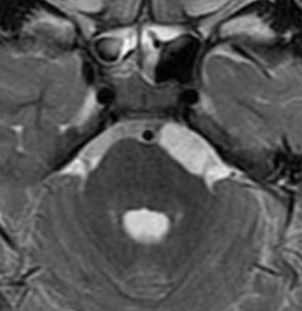

МРТ имеет большие диагностические возможности. В типичных случаях в зоне локализации опухоли выявляют в Т1W низкоинтенсивный сигнал, а в Т2W-высокоинтенсивный сигнал, не изменяющийся после контрастирования гадолинием. Сигнал не всегда отличим от ликвора, что затрудняет постановку диагноза ЭО. Так, Shinoda и соавторы в 1995 г. описывали случай, когда у больного с тригеминальной невралгией была интраоперационно обнаружена ЭО мостомозжечкового угла, недиагностированная при МРТ [37]. В связи с этим, выделяют дополнительные признаки ЭО при МРТ: 1) минимальный масс-эффект при больших размерах опухоли; 2) неровный "зубчатый" контур очага; 3) отсутствие перитуморального отека; 4) гидроцефалия обычно не выражена и не соизмеряется с размерами опухоли; 5) сигнал не изменяется после контрастирования [45].

Проявления на МРТ схожи с таковыми на КТ; эпидермоиды часто неотличимы от арахноидальных кист или расширенных ликворных пространств на многих последовательностях.

- T1

- обычно изоинтенсивны ликвору

- часто наблюдается более интенсивный сигнал по сравнению с ликвором по периферии образования

- обычно изоинтенсивны ликвору (65%)

- обычно неоднородный / "грязный" сигнал; выше, чем от ликвора